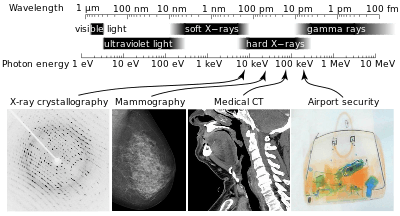

X-rays are part of the electromagnetic spectrum, with wavelengths shorter than visible light. Different applications use different parts of the X-ray spectrum.

X-radiation (composed of X-rays) is a form of electromagnetic radiation. Most X-rays have a wavelength ranging from 0.01 to 10 nanometers, corresponding to frequencies in the range 30 petahertz to 30 exahertz (3×1016 Hz to 3×1019 Hz) and energies in the range 100 eV to 100 keV. X-ray wavelengths are shorter than those of UV rays and typically longer than those of gamma rays. In many languages, X-radiation is referred to with terms meaning Röntgen radiation, after Wilhelm Röntgen,[1] who is usually credited as its discoverer, and who had named it X-radiation to signify an unknown type of radiation.[2] Spelling of X-ray(s) in the English language includes the variants x-ray(s), xray(s), and X ray(s).[3]

X-rays with high photon energies (above 5–10 keV, below 0.2–0.1 nm wavelength) are called hard X-rays, while those with lower energy are called soft X-rays.[4] Due to their penetrating ability, hard X-rays are widely used to image the inside of objects, e.g., in medical radiography and airport security. The term X-ray is metonymically used to refer to a radiographic image produced using this method, in addition to the method itself. Since the wavelengths of hard X-rays are similar to the size of atoms they are also useful for determining crystal structures by X-ray crystallography. By contrast, soft X-rays are easily absorbed in air; the attenuation length of 600 eV (~2 nm) X-rays in water is less than 1 micrometer.[5]